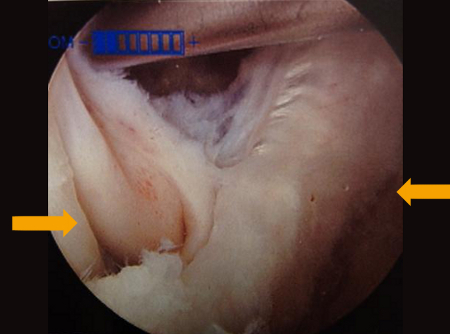

[Figure caption and citation for the preceding image starts]: Intervalo do gastrocnêmio medial e semimembranoso visto com artroscópioDo acervo do Dr John D. Kelly IV; usado com permissão [Citation ends].